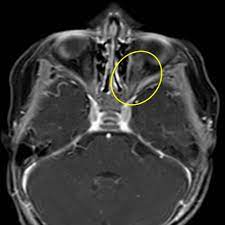

Convolvulaceae - Morning-glory family. Graphically this is identified on an axial image at the level of the midbrain by drawing 1. These old-fashioned favorites love to climb.